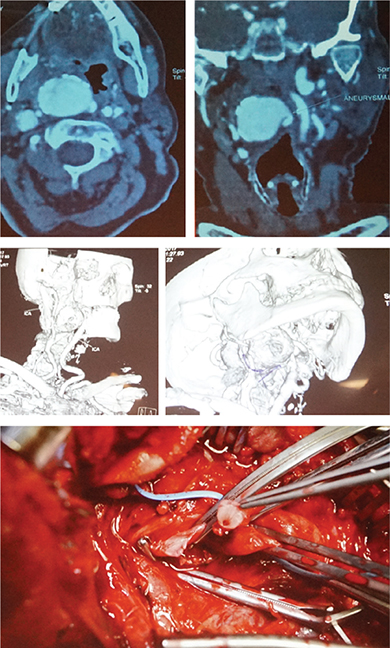

Окрема секція була присвячена досягненням косметологічної (дерматологічної) хірургії. Відзначимо доповідь щодо використання наножиру та розроблення нових препаратів у лікуванні пацієнтів із келоїдними рубцями шкіри. Серед цікавих клінічних випадків — доповідь про хірургічне лікування аневризми внутрішньої сонної артерії. Використання площинної остеотомії нижньої щелепи та мікрохірургічної техніки дозволило створити адекватний хірургічний доступ до аневризми і видалити вражену ділянку судини.